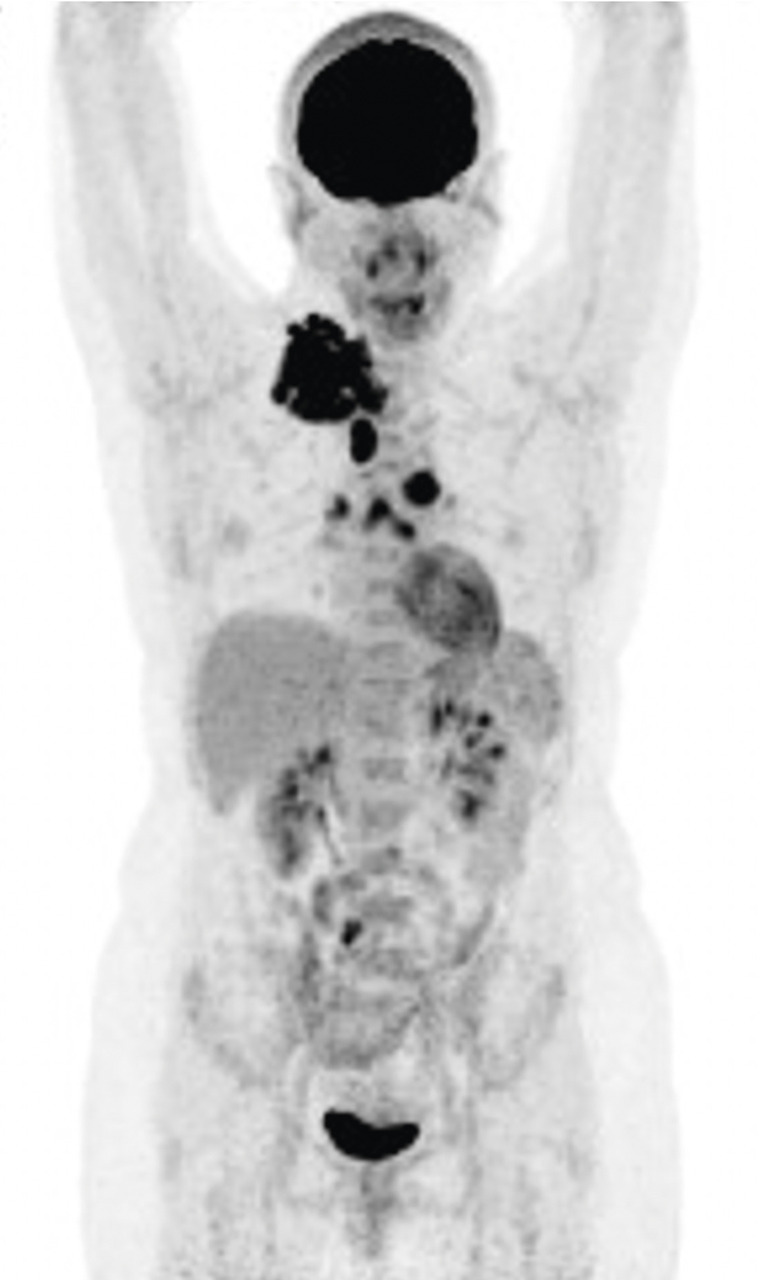

Le bilan d’extension est très codifié, avec la réalisation des examens d’imagerie : la tomographie par émission de positons (TEP) au 18 fluorodésoxyglucose est désormais obligatoire au moment de la prise en charge initiale (voir l’article « Tomographie par émission de positons : une place centrale dans le bilan et l’évaluation », p. 621).

Grâce aux données obtenues par la tomographie par émission de positons/tomodensitométrie (TEP/TDM), il n’est pas nécessaire de réaliser de bilan médullaire (myélogramme et biopsie ostéomédullaire) au moment de la prise en charge initiale. Cela permet d’éviter un geste qui peut être douloureux et dont les résultats ne modifient pas la décision thérapeutique.